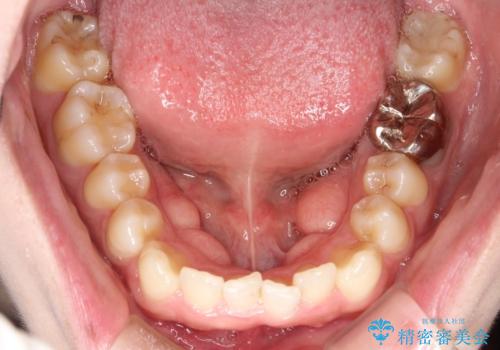

- 八重歯を治したいとのことで来院されました。

右上の犬歯が外側に飛び出して、二番目の歯が内側に入っている状態でした。

上の奥歯を後方に移動させてスペースを確保して、前歯のガタガタを改善する計画としました。